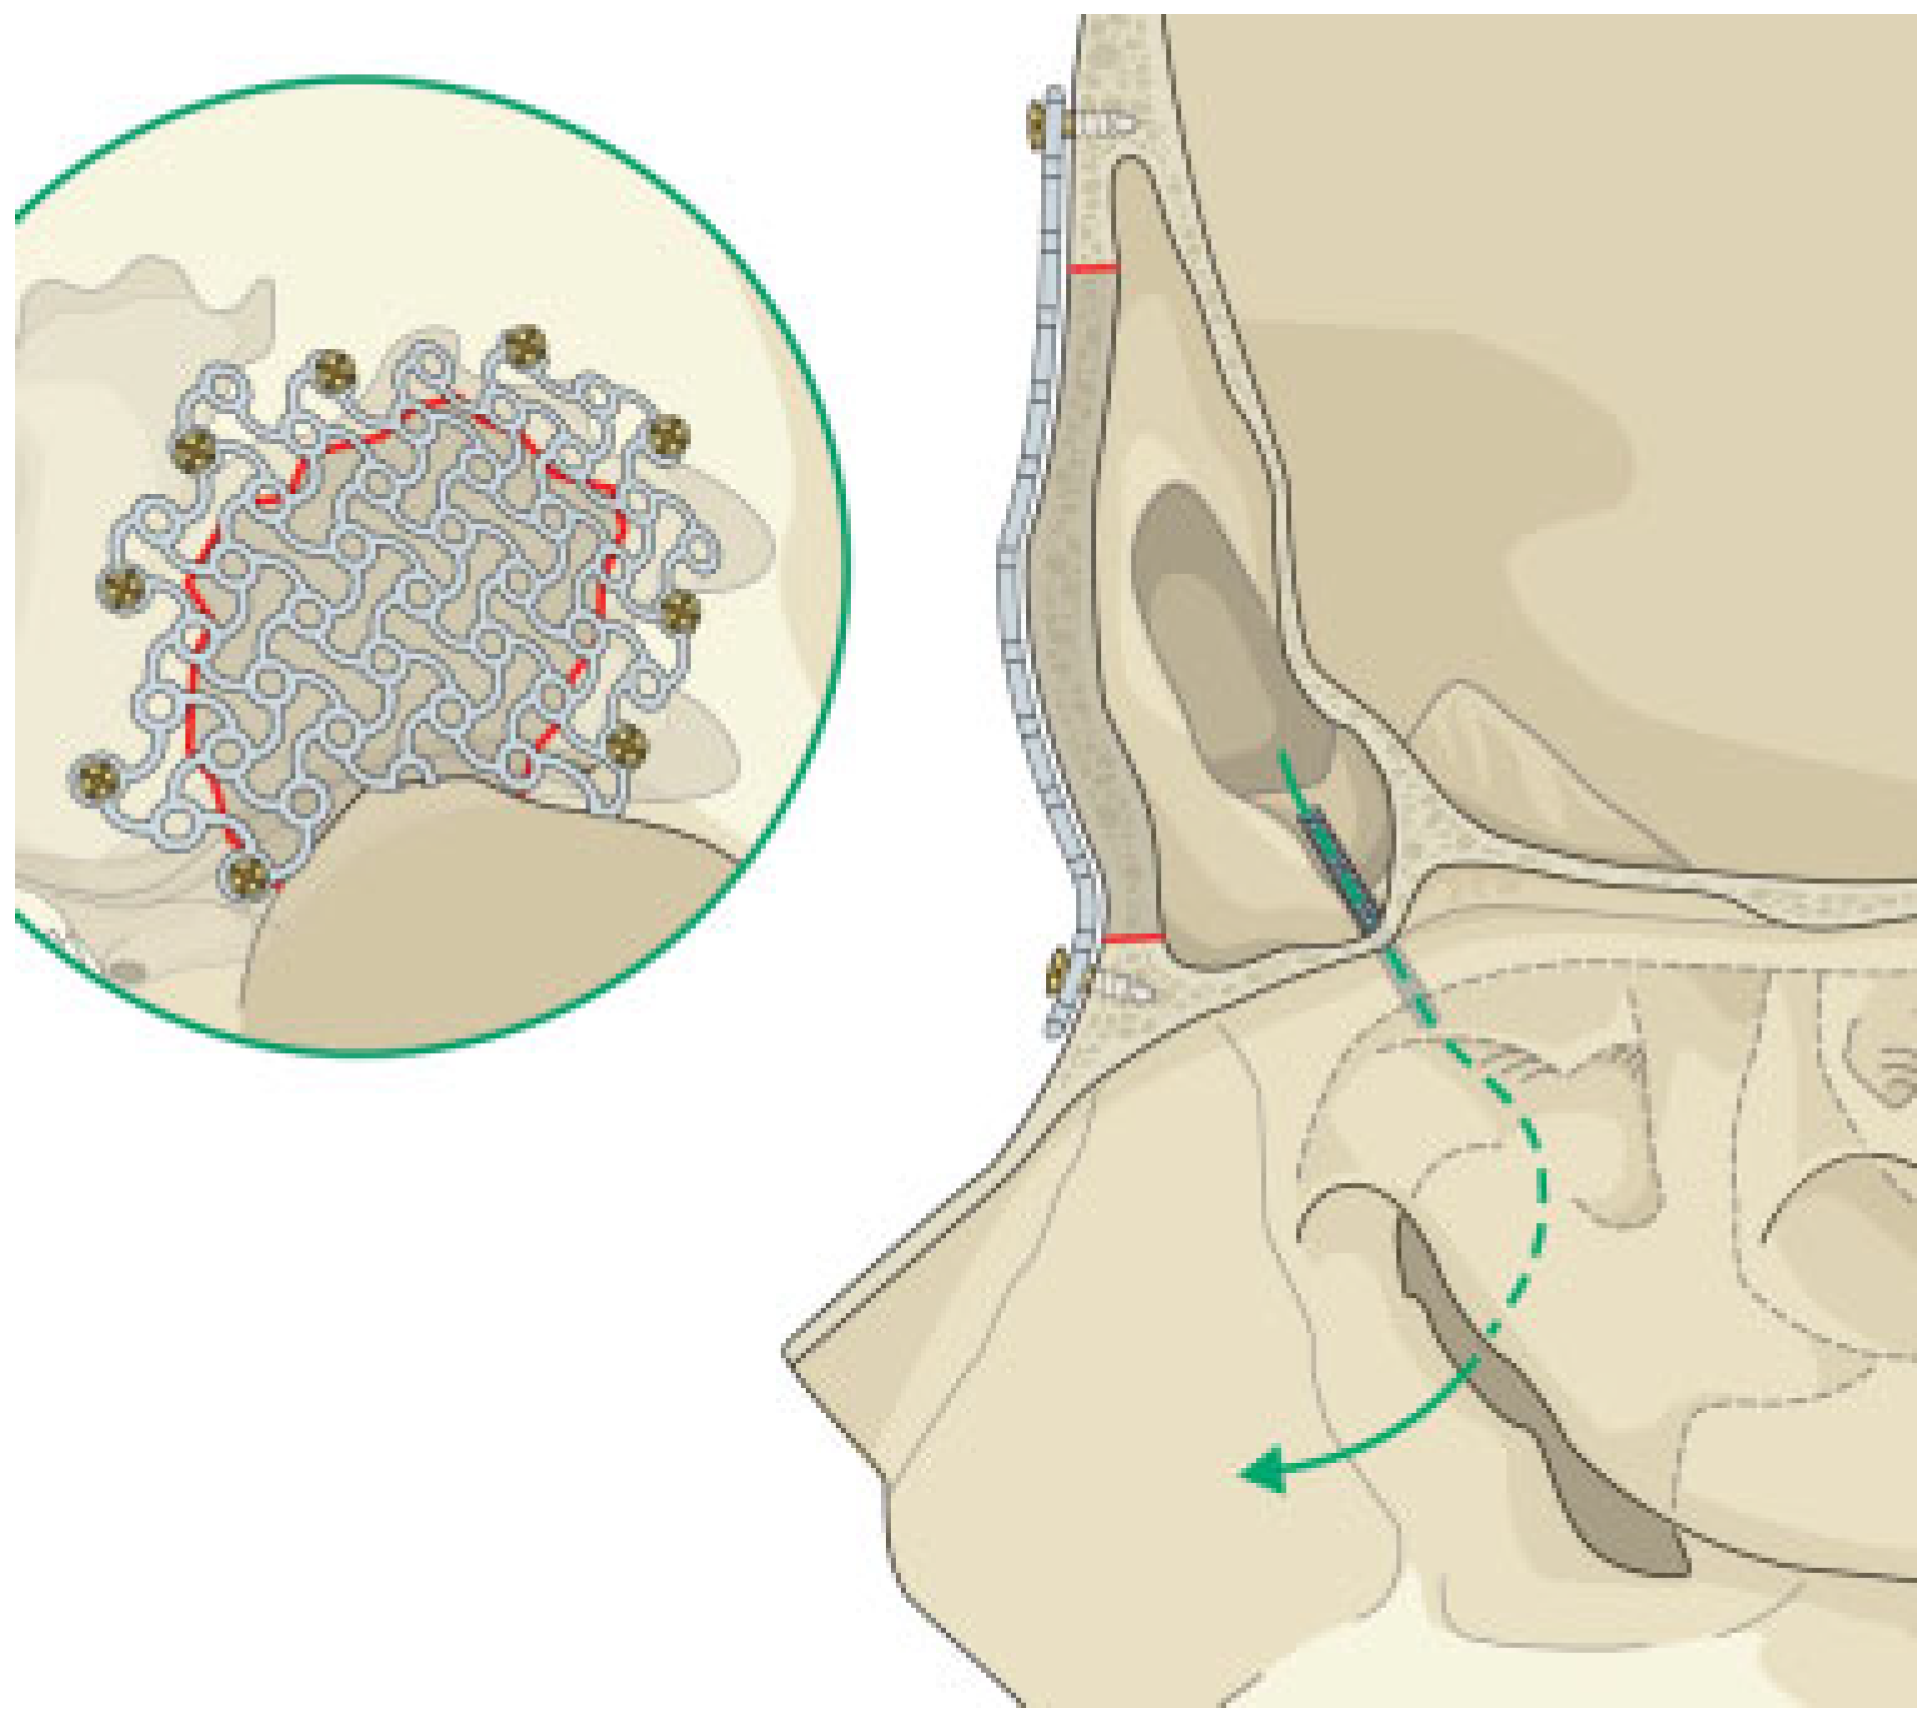

Open Surgical Management of an Asymptomatic Giant Frontal Sinus Osteoma

:Case Report